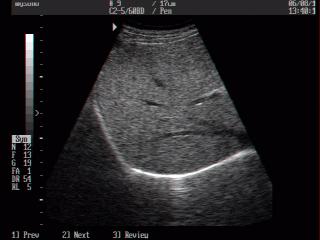

Atlas of ultrasound images - abdomen (pg. 7)

In the section "Abdominal ultrasonography" of atlas the results of ultrasound examinations of abdominal cavity organs are represented. Here you can see images of gall bladder, liver, kidney and intestine, the sonograms: ureter stone, intrahepatic calcification, hemangioma, enlarged spleen, etc.